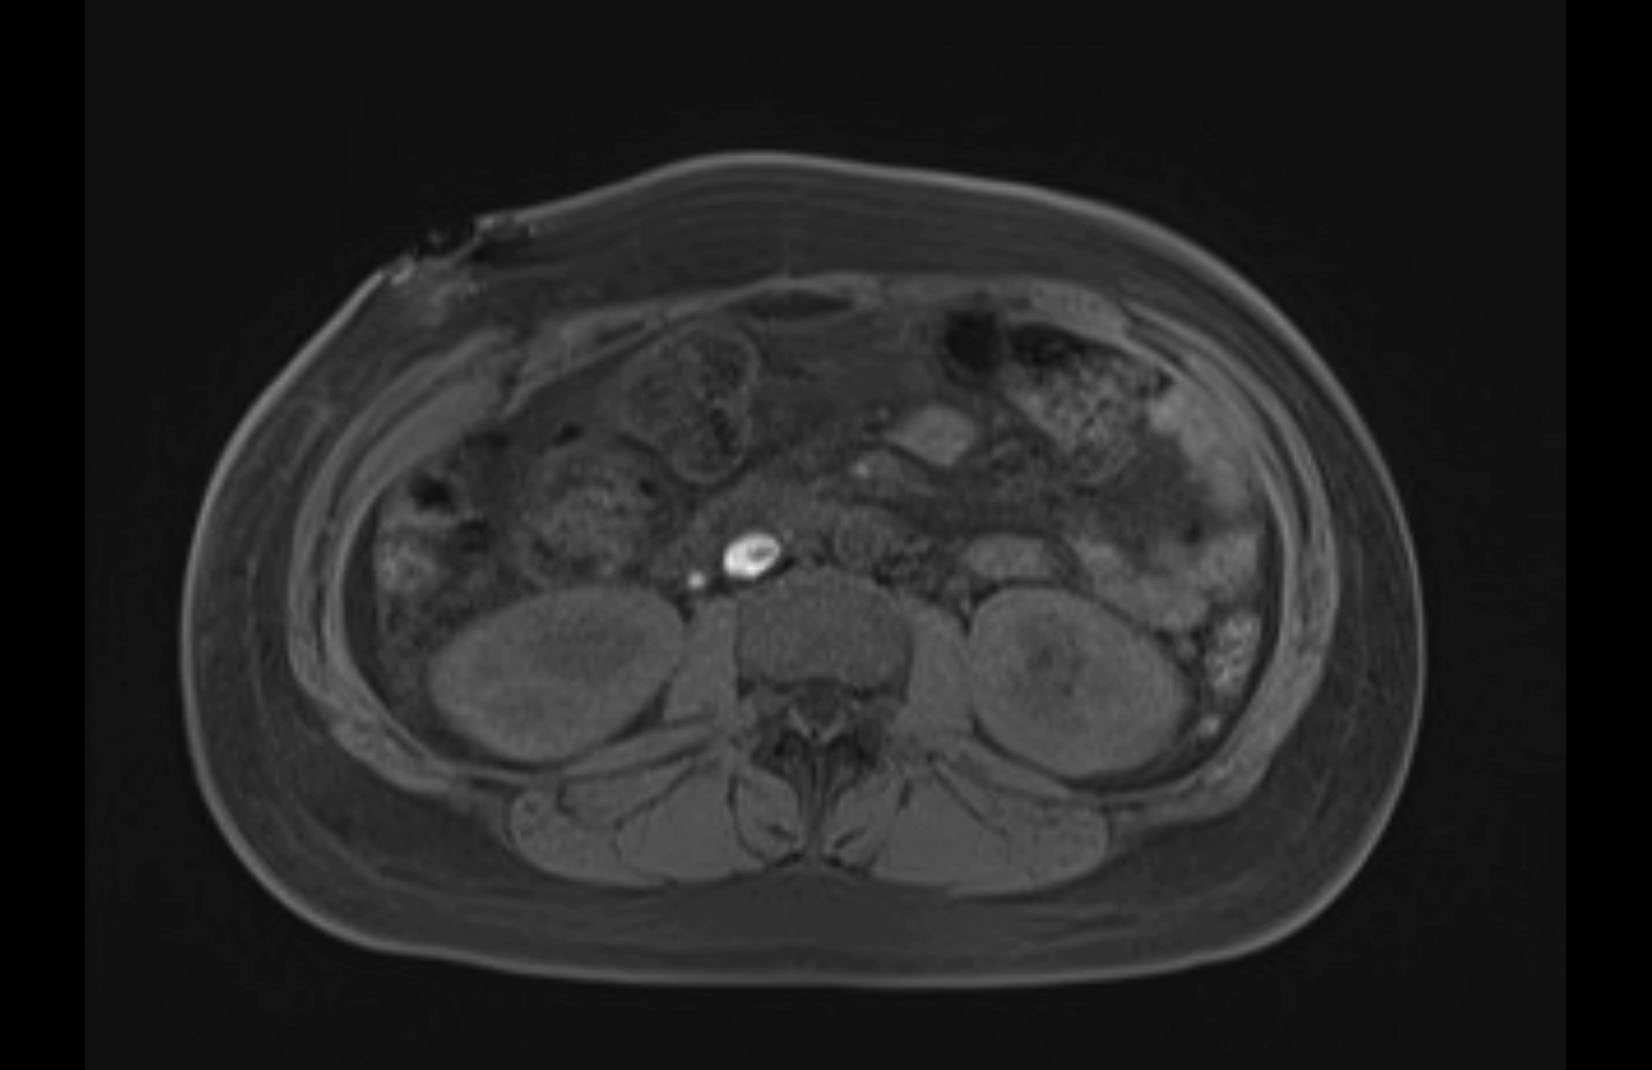

MRI T1

MRI T2

Imaging analysis

Based on initial findings, which issue(s) would you be most concerned about?